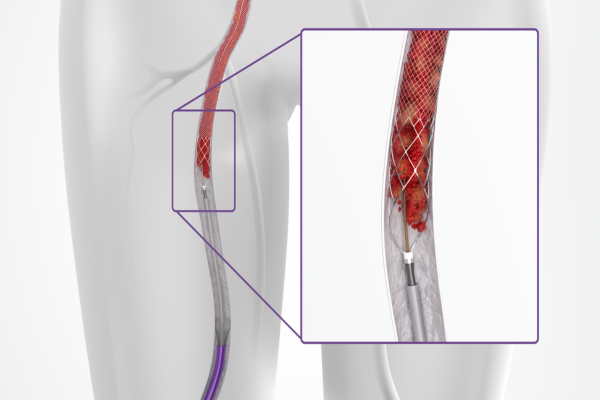

Pulmonary embolism occurs when large blood clots block lung arteries, causing sudden breathlessness, chest pain, and collapse.

Thrombectomy removes the clot directly, restores blood flow, reduces strain on the heart, and saves life in high-risk patients.